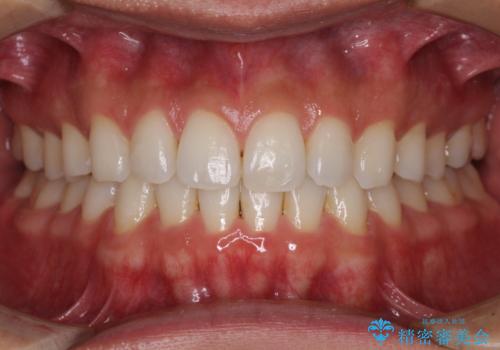

- 上下前歯の後戻りを気にして来院された患者様です。

インビザラインでの治療を希望されていて、デコボコの程度が中等度であり、安価なパッケージにて対応可能と判断されたため、インビザライン・モデレートを用いて矯正治療を行うこととしました。

インビザライン・モデレートは、製作できるアライナーの枚数に制限があるため、移動可能な量に限りがあるものの、インビザライン・ライトよりも枚数が多いため、幅広い症例に対応可能です。